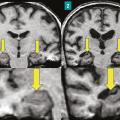

Il pourrait apparaître désuet de s’intéresser à l’anatomie macroscopique de la mémoire. Les mécanismes intimes de cette fonction cérébrale complexe mettent en effet en jeu des circuits neuronaux et des phénomènes de neurogenèse qui relèvent de mécanismes survenant à l’échelle microscopique.Néanmoins, certaines structures anatomiques…

1 - Les phénomènes mnésiques mettent en jeu à l’échelle microscopique des circuits neuronaux et des processus de neurogenèse. Néanmoins, certaines structures anatomiques clés comme l’hippocampe ou le lobe limbique ont un rôle central. L’hippocampe intervient dans l’acquisition, le stockage et la distribution des informations…